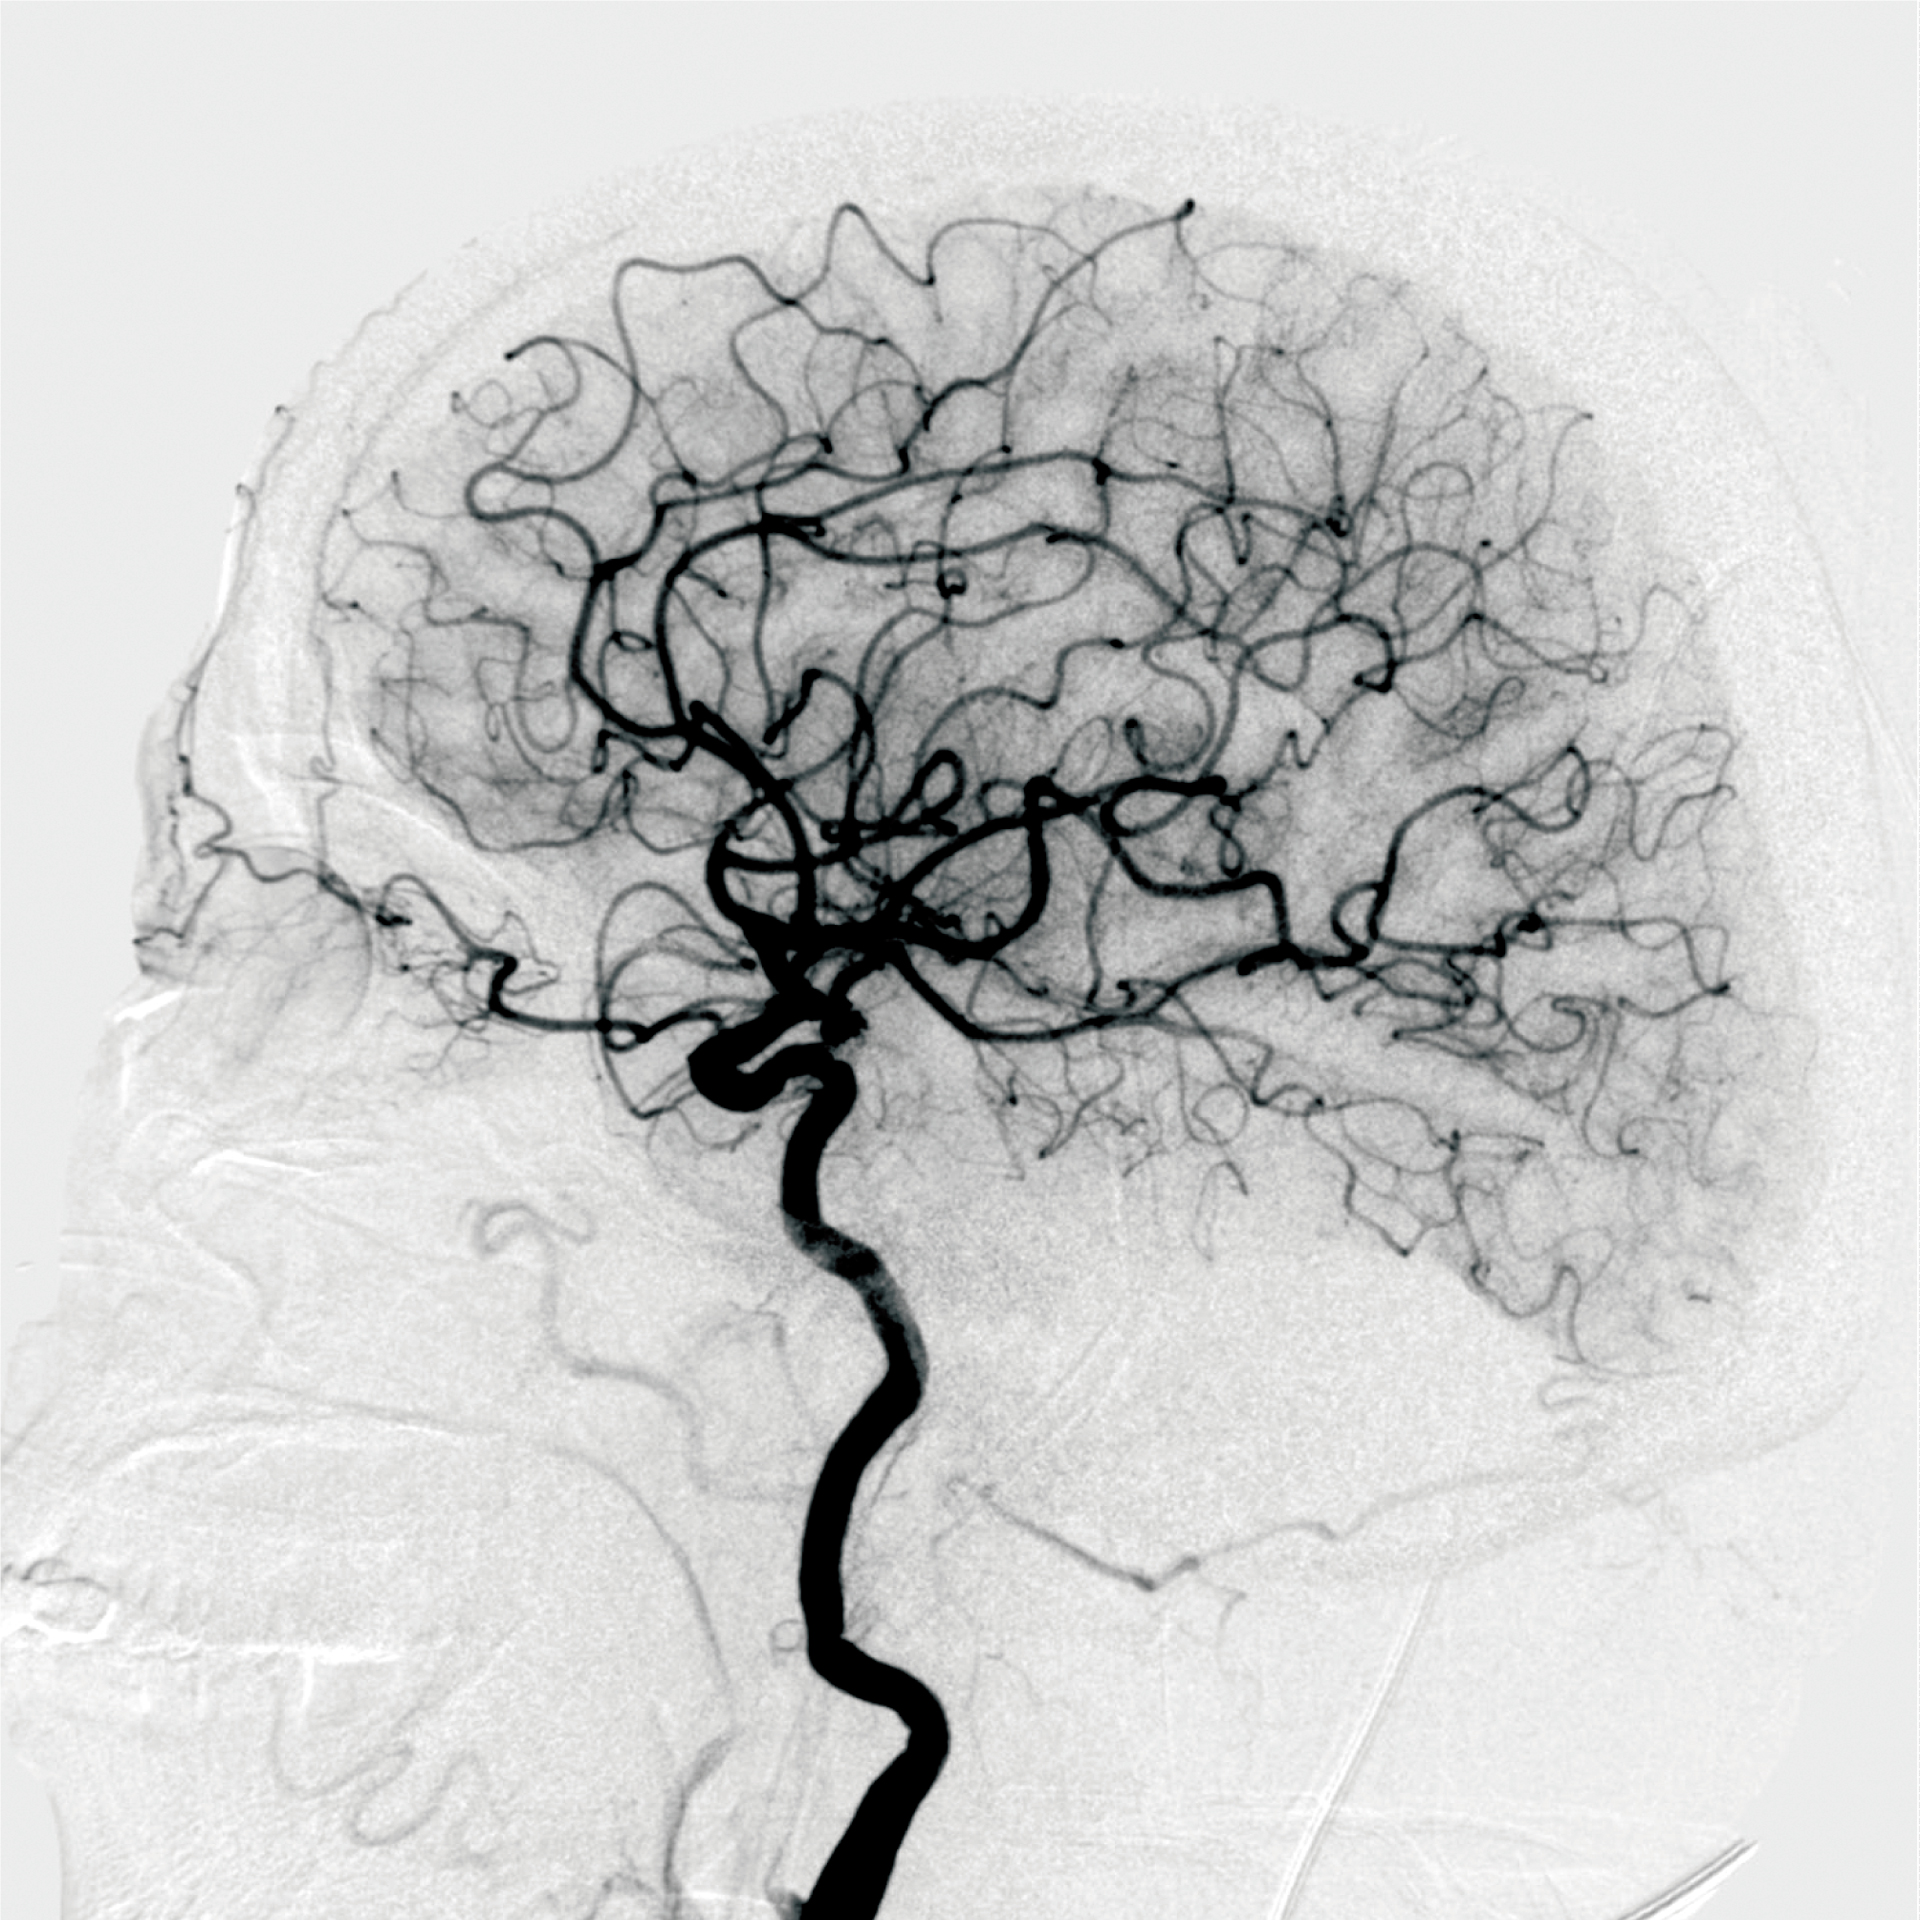

DSA造影-神經(jīng)血管-唯邁醫(yī)療極光平板DSA供圖